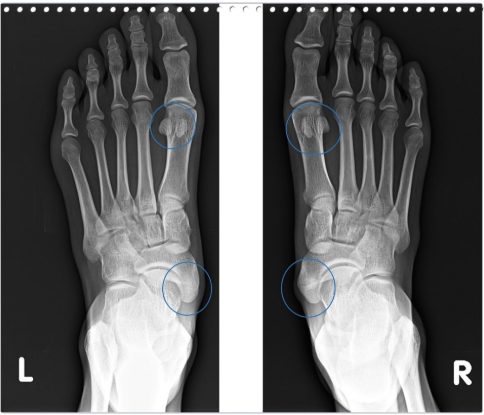

평발이나 요족처럼 발바닥 아치가 무너지거나 과도하게 높아지는 현상은 척추와 관절 건강에도 중요한 신호가 됩니다.

평발은 걸을 때 다리가 안쪽으로 돌아가고, 이 힘이 골반을 앞으로 기울이면서 척추까지 영향을 줄 수 있습니다.

요족은 반대로 발바닥에 압력이 한쪽으로 치우치면서 무릎과 고관절이 불안정해지기 쉽습니다.